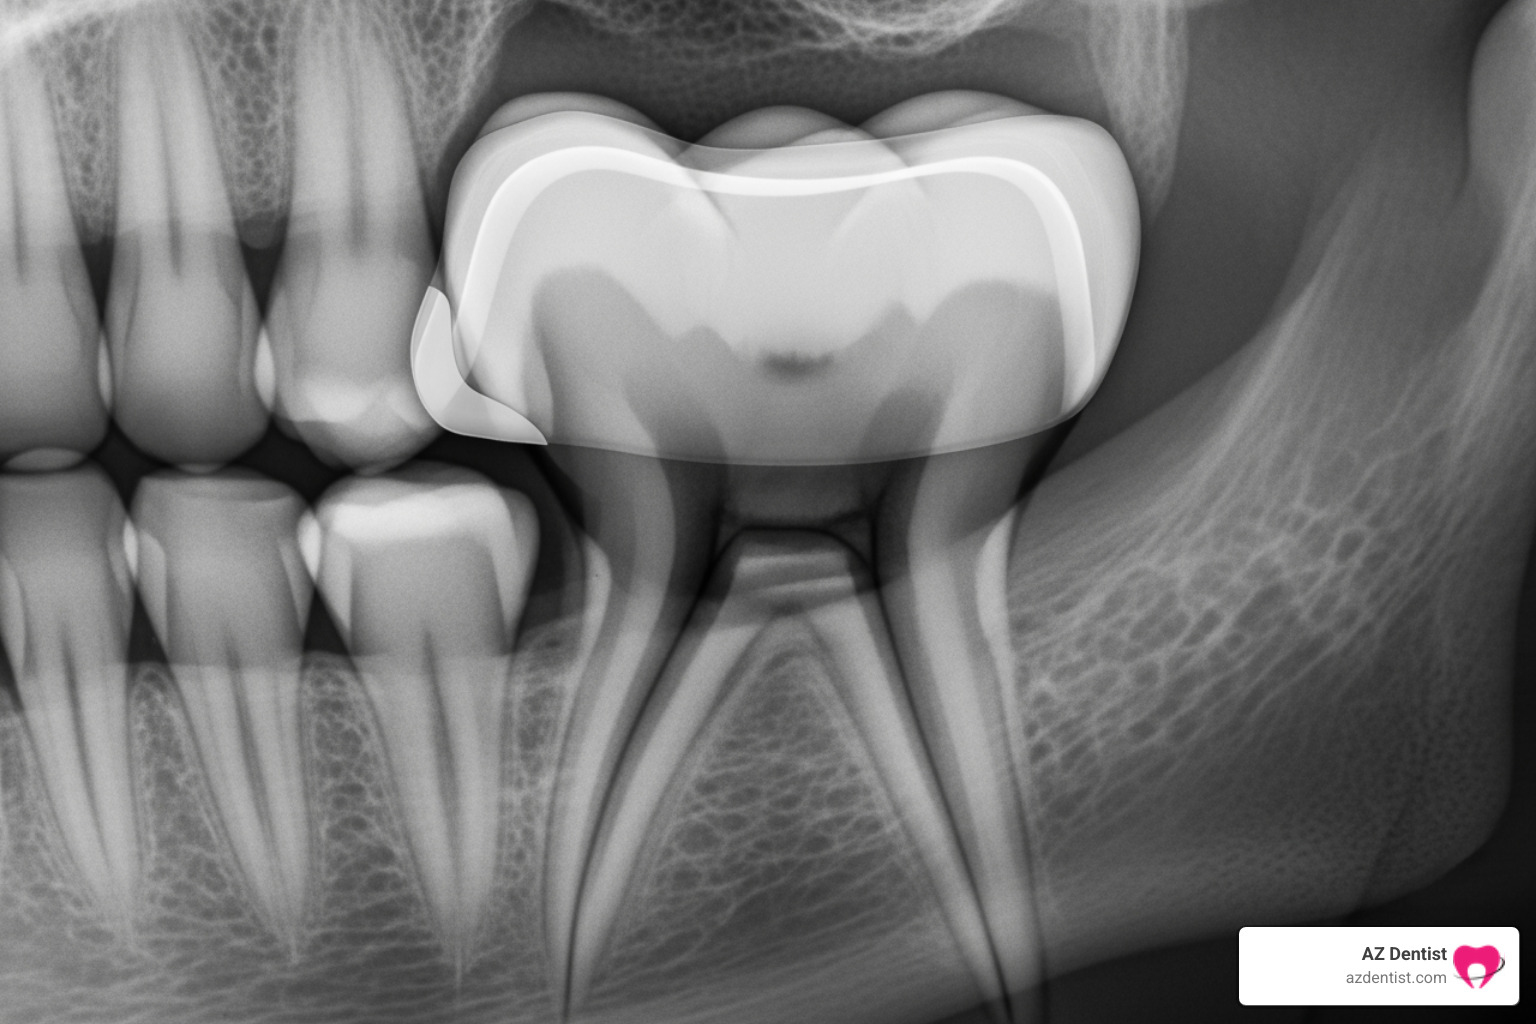

- Recurrent Decay: It’s a common misconception that a crowned tooth is immune to decay. While the crown material itself doesn’t decay, decay can still form at the border where the crown meets your natural tooth. This happens if the seal between the crown and tooth isn’t perfect, allowing bacteria to penetrate. Decay can form at the crown’s border and lead to persistent pain. If this decay progresses and reaches the nerve, it can cause significant dental crown pain and may even necessitate a root canal.

- Nerve Inflammation or Infection (Abscess): Sometimes, the tooth preparation process (which involves removing some tooth structure to make room for the crown) can traumatize the nerve, leading to inflammation and sensitivity. This is particularly true if the tooth had deep decay or a large filling beforehand. If bacteria reach the nerve, an infection can develop, potentially leading to an abscessed tooth. This usually presents as throbbing pain, sensitivity to hot and cold, and sometimes swelling or a “pimple” on the gums. If you didn’t have a root canal before the crown, an infection is a significant concern.

- Cracked or Fractured Tooth Root: A cracked tooth or even a hairline fracture in the root beneath the crown can cause mild to severe pain. This pain might be especially noticeable when chewing or when the tooth is exposed to hot or cold temperatures. A cracked crown or tooth underneath a crown can cause mild pain. These fractures can be difficult to diagnose but are crucial to address as they can lead to infection and further tooth damage. For more information on cracked teeth, we recommend checking out resources from the American Association of Endodontists.